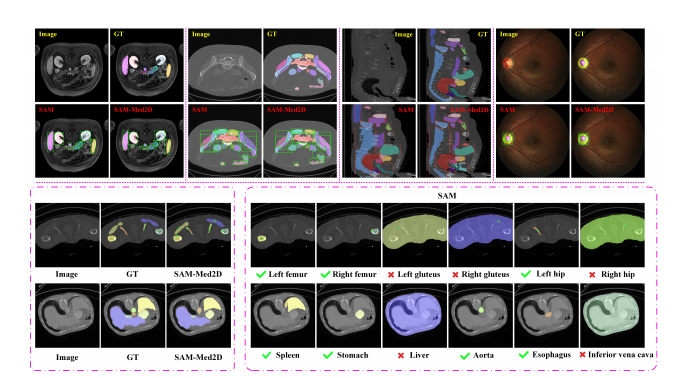

深度学习图像分割技术在医学影像诊断中的应用已成为现代医学研究和临床实践中的重要突破。图像分割旨在将医学图像中的感兴趣区域(如肿瘤、器官或病变)从背景中分离出来,进而辅助诊断、治疗规划和术后评估。随着深度学习技术,尤其是卷积神经网络(CNN)和变压器网络(Transformer)的不断进步,医学影像的自动分割和分析得到了显著提升,不仅提高了诊断的准确性,还节省了大量的时间和人力成本。本文将详细探讨深度学习图像分割技术在医学影像中的关键作用,并通过一些实际应用案例来展示其效果。

深度学习中的图像分割技术使用神经网络对图像进行像素级分类,将图像中的不同区域区分开来。与传统的基于阈值、边缘检测和区域生长等图像处理方法不同,深度学习方法通过学习数据中隐含的特征,能够在复杂环境下实现更高效、精确的分割。

卷积神经网络是深度学习中应用最广泛的网络结构之一,尤其在图像处理任务中表现突出。CNN通过卷积层提取图像中的空间特征,再通过池化层降低特征维度,最终通过全连接层输出分类结果。在图像分割任务中,常见的网络结构包括:

- U-Net:一种用于医学图像分割的经典网络架构,具有对称的编码器-解码器结构,能够有效恢复图像的空间信息。